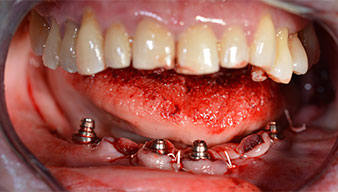

After removal of the residual dentition in the mandible, the alveolar crest was exposed from 37 to 47.

The mental foramen was first identified as a limiting anatomical structure and then the cortical bone of the crest was smoothed with the straight handpiece and a large rose-head bur (Fig. 4).